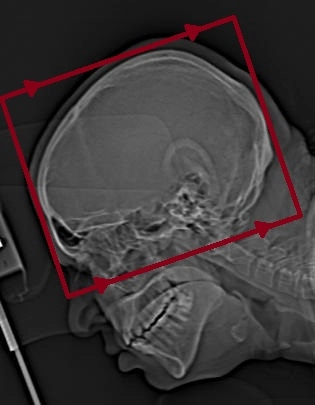

Supra Orbito Meatal Hat

Beyin BT Aksiyal

Beyin BT Koronal